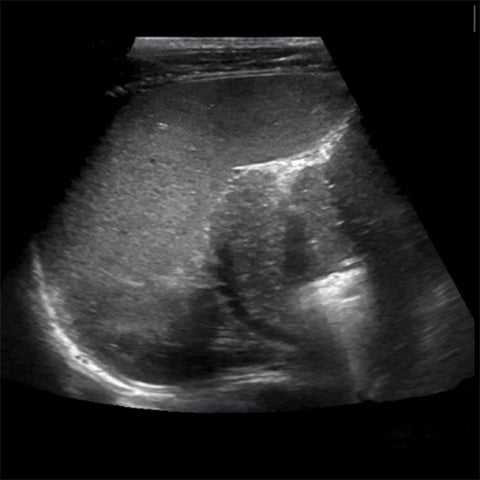

Today we are thankful for clearly visualized pancreas .We can give you visual instruction.